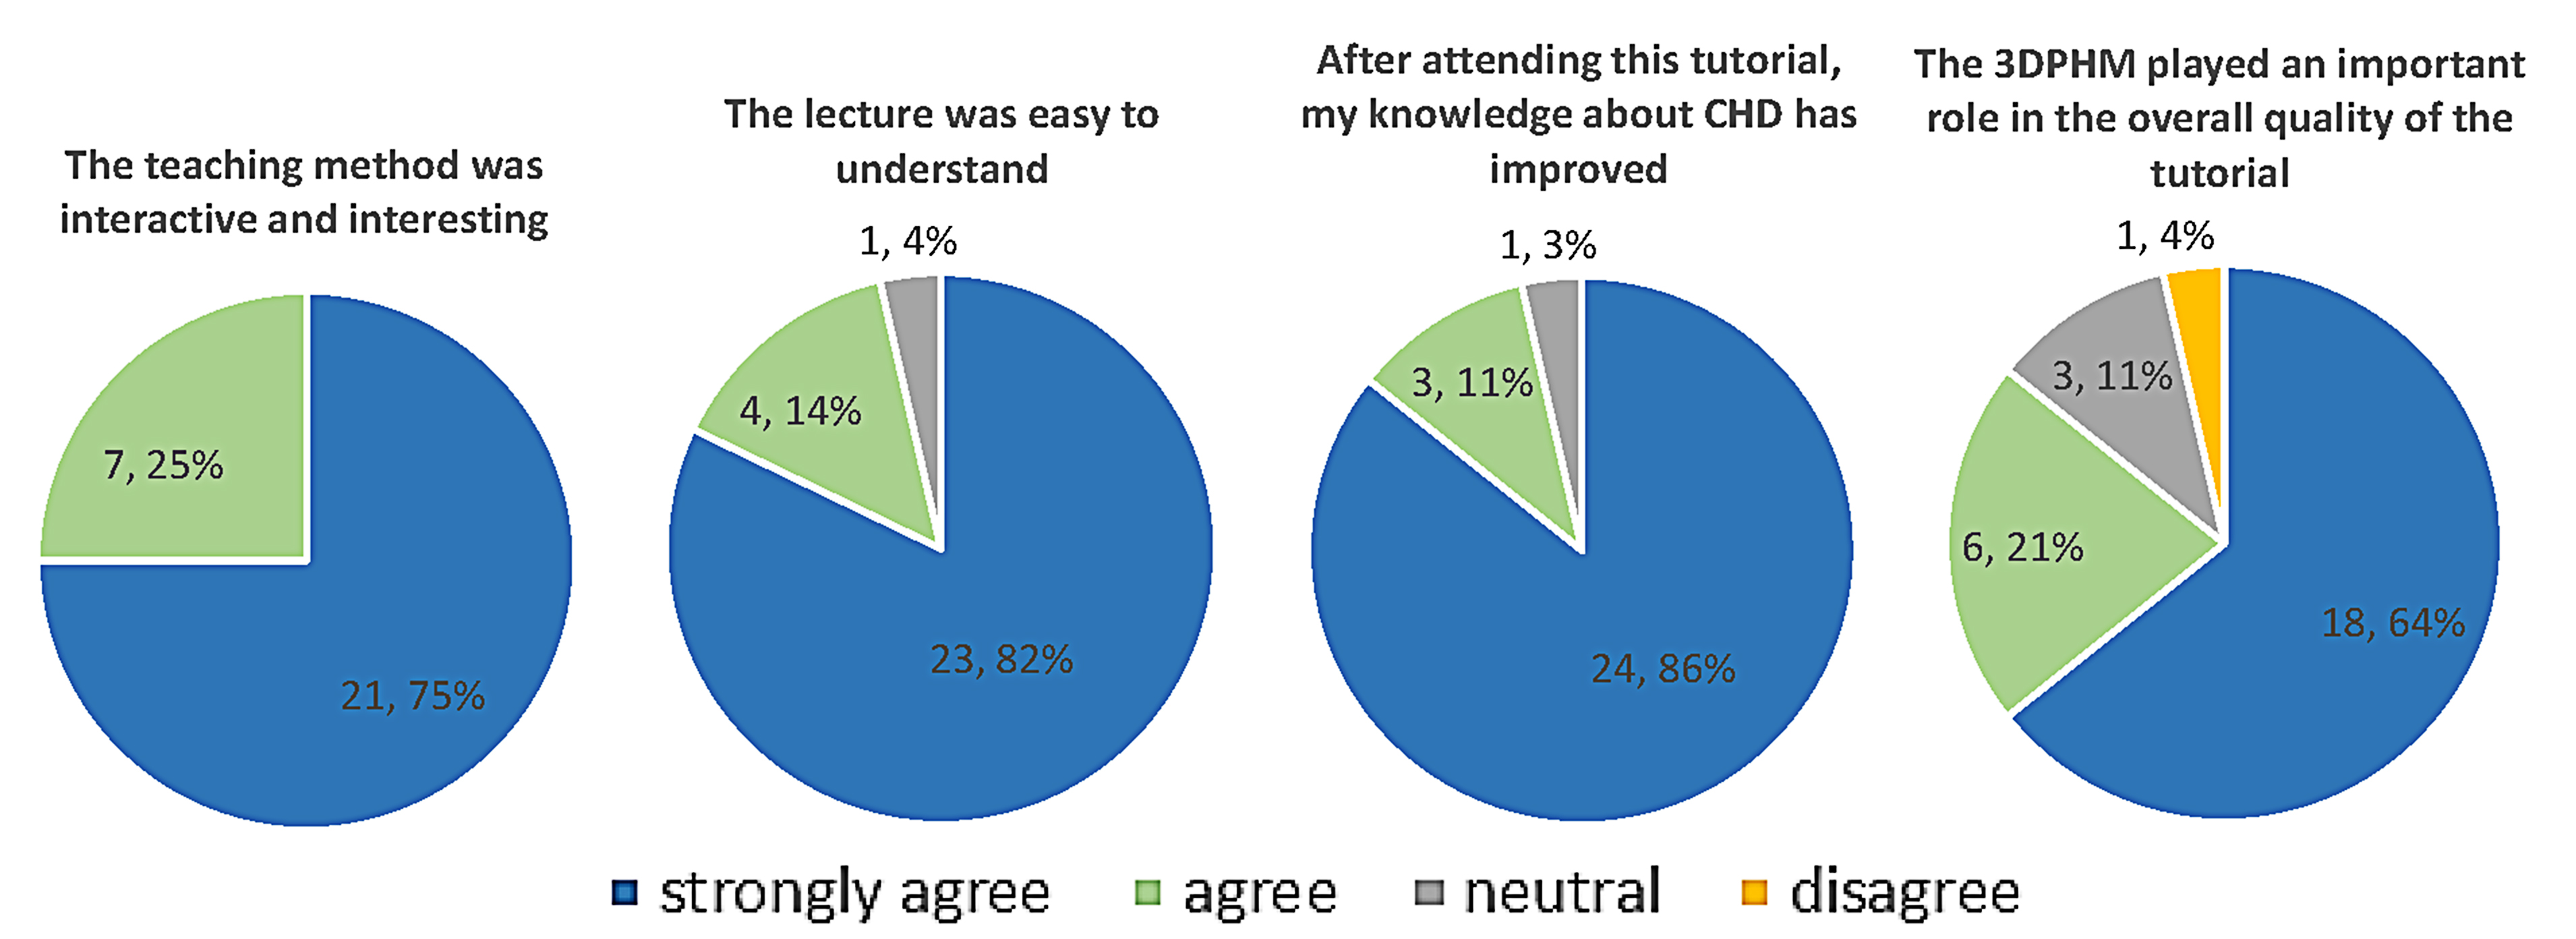

In comparing survey responses between the control and 3DPHM groups, the Mann-Whitney U test showed no significant difference in all of the questions. Figs. 7,8 illustrate the survey responses in percentage for the control group and 3DPHM group, respectively. Both groups of students indicated either ‘strongly agree’ or ‘agree’ that the teaching method was interactive and interesting (U = 346.5, p = 0.93). Slightly more students in 3DPHM group indicated ‘strongly agree’ that the education was easy to understand (82%) compared to the control group (76%), although this is not statistically significant (U = 331.5, p = 0.64). More students in 3DPHM indicated ‘strongly agree’ that their knowledge about CHD has improved (86%) compared to the control group (68%), and again this is not statistically significant (U = 292, p = 0.16). About 64% of the students in 3DPHM group indicated ‘strongly agree’ that the 3DPHM played an important role in helping them understand CHD. This is similar to the control group where 60% indicated ‘strongly agree’ that the 3DPHM would help them to understand CHD (U = 349.5, p = 0.99). However, one student in the 3DPHM group disagreed that the 3DPHM helped in his/her learning of CHD.

Fig. 8.

Fig. 8.Survey responses (number of students, percentage) of the 3DPHM group with regards to the education session. 3DPHM, three-dimensional printed heart model; CHD, congenital heart disease.

As for the survey responses, although not statistically significant, greater percentage of students in 3DPHM group responded that the lecture was easy to understand, and that their knowledge on the topic of CHD has improved. In Loke et al.’s [2] study, the 3DPHM group rated significantly higher satisfaction score towards the teaching session, when compared to the control group. On the other hand, a meta-analysis found that the 3DPHM is associated with higher subjective evaluation scores and satisfactory level among the study participants [9]. This is also reflected in our study in which majority of the students responded (96% in the control group and 85% in the 3DPHM group) ‘agree’ or ‘strongly agree’ that the 3DPHM had helped them to gain a deeper understanding of CHD. Hence, the 3DPHM has contributed to improving students’ learning experience.